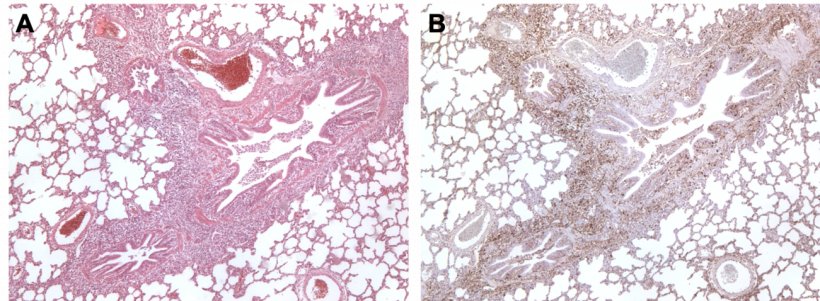

Im Falle einer Koinfektion mit M. hyopneumoniae und PCV2 hat sich gezeigt, dass M. hyopneumoniae die Schwere der durch PCV2 hervorgerufenen Läsionen in der Lunge und den lymphatischen Organen mildert und eine stärkere Virusvermehrung sowie seine Persistenz in den Geweben fördert (Abb. 3), wodurch sich die Inzidenz von PCV2-bedingten systemischen Erkrankungen (aktuelle Bezeichnung für PMWS, engl. Postweaning Multisystemic Wasting Syndrome) erhöht.

Abbildung 3: Mit M. hyopneumoniae und PCV2 koinfizierte Lunge eines Schweins A: Bereich der peribronchiolären lymphatischen Hyperplasie, verursacht durch M. hyopneumoniae. B: Große Mengen des PCV2-Antigens im Bereich der lymphatischen Hyperplasie.